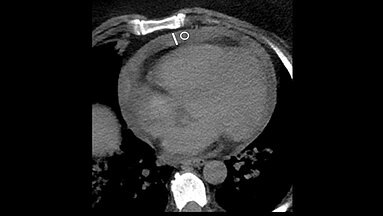

Recent advancements in MRI techniques and tumor biology have led to updated hepatocellular carcinoma (HCC) diagnostic guidelines from various liver study associations. Conducted across 11 South…